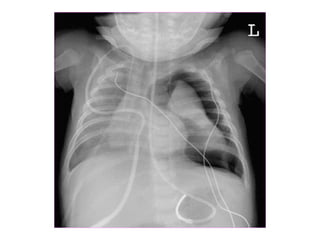

Chest x ray